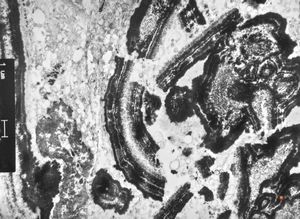

M,66y. | follicular cyst with hyaline Rushton bodies